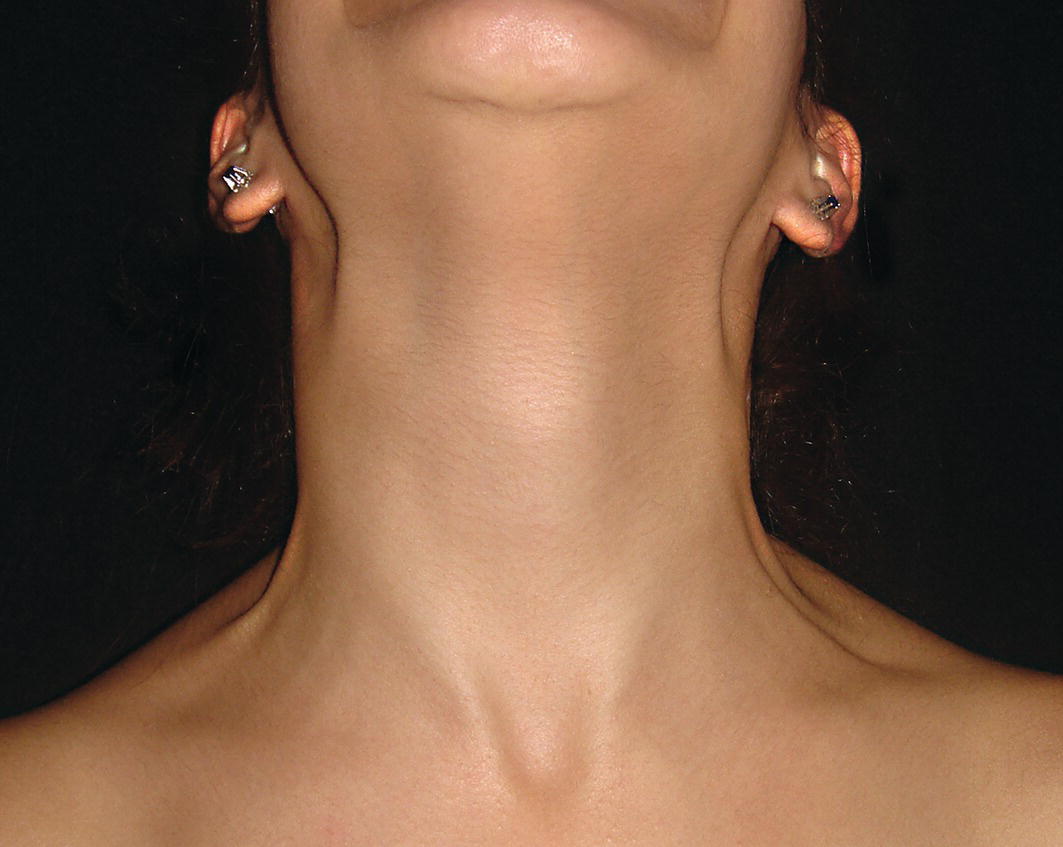

The morphology of the upper aspect of the neck and its transition with the submental region has a major impact on the aesthetics of the lower face. The anterior part of the neck extends no higher than the inferior border of the mandible. The hyoid bone is connected to the mandible by a thin sheet of muscle, the mylohyoids, which form the upper limit of the anterior part of the neck and separate the mouth from the neck. Superficially (i.e. below the mylohyoids) lies the anterior belly of digastric, while lying above it, half hidden under the mandible in the submandibular fossa, is the submandibular salivary gland (Figure 21.1). These structures are covered in by the investing layer of deep cervical fascia, which is attached to the hyoid bone and the inferior border of the mandible. The platysma muscle lies in the subcutaneous tissues. It forms a broad, flat sheet, extending from the deep fascia over the upper part of pectoralis major and the most anterior part of deltoid to the inferior border of the mandible, with some fibres reaching the lateral part of the lower lip. The sternocleidomastoid muscle forms a prominent neck landmark and may be made to stand out by turning the head towards the opposite side against resistance. The two heads of origin are from the sternum and medial one‐third of the clavicle; its attachment is to the mastoid process, which forms a readily visible and palpable bony landmark behind the lobe of the ear (Figure 21.2). Figure 21.1 Submental anatomy in relation to the mandible, with muscle attachments: Despite its importance in facial aesthetics, there is much confusion in terminology relating to the description and analysis of the submental‐cervical region. For example, the cervicomental angle has been described by perhaps half a dozen different methods, depending on the describing authority. Appropriate terminology is essential for the evaluation and accurate description of submental‐cervical aesthetics (Figure 21.3). Figure 21.2 Profile view of the face and neck with superimposed bony and muscular outlines: Cervical point (C‐point or ‘point C’): The innermost (posterior‐superior) point between the submental plane and the anterior aspect of the neck in the midsagittal plane, located at the intersection of lines drawn tangent to the submental region and the anterior neck. Submental plane: A plane or line constructed between the cervical point (C‐point) and the most inferior point on the chin (soft tissue menton, Me’). If C‐point cannot be defined, the submental plane is drawn tangent to the submental contour passing through soft tissue menton. The submental plane is referred to as the ‘throat’ plane by some authorities; the submental length (distance from C‐point to menton) is therefore sometimes referred to as the ‘throat length’. Cervical plane: A plane or line drawn tangent to the anterior soft tissue contour of the neck above and below the thyroid prominence. Figure 21.3 Submental plane, cervical plane and cervical point (C‐point). A thorough understanding of the aetiological factors involved in creating a poor aesthetic contour of the submental‐cervical region is required in order to diagnose and appropriately plan the correction of the aesthetic submental‐cervical angles and contour. The tonicity of the submental‐cervical skin, the muscular support of the neck, the isolated fatty deposits in the submental‐cervical region, the skeletal framework of the mandible and chin, and the spatial position of the hyoid bone are all important parameters in the aesthetic analysis of the submental‐cervical region. An undesirable submental‐cervical contour may result from: It is paramount that the clinical evaluation is undertaken with the patient in natural head position (NHP). Even a small degree of upward or downward tilting of the head must be avoided as it may have a profound effect on the contour of the submental‐cervical region. A number of parameters may be analysed in the clinical evaluation of the submental‐cervical region: Mandibular and/or chin deficiency in the sagittal plane, and/or posterior (downward and backward) rotation of the mandible, often secondary to vertical maxillary excess, may contribute to the undesirable aesthetic appearance of the submental‐cervical region (Figure 21.4). It is helpful to have the ‘Class II skeletal pattern’ patient posture the mandible forward to a more normal sagittal position, which will concurrently stretch the submental soft tissues. If this manoeuvre improves the submental‐cervical aesthetics visually, and tightens the submental soft tissues to palpation, then correction of the underlying skeletal discrepancy is likely to improve the submental‐cervical aesthetics (Figure 21.5). Figure 21.4 Class II jaw relationship due to mandibular deficiency and significant compensatory proclination of the mandibular incisor teeth; the submental‐cervical angle is increased. Figure 21.5 (A) Patient with Class II jaw relationship due to mandibular deficiency. (B) Posturing the mandible forward to a more normal sagittal position will concurrently stretch the submental soft tissues. Figure 21.6 Skin laxity test. The converse is also true. Surgical procedures to set back the mandible, or set down the maxilla causing posterior mandibular rotation, will tend to have undesirable consequences on submental‐cervical aesthetics (see Figure 19.22). The patient must be informed of these potential untoward consequences of orthognathic surgery, and should be advised of the possible future need for aesthetic surgical procedures of the submental‐cervical region. The laxity of the submental‐cervical skin may be evaluated by the skin laxity test: the clinician stands behind the patient and gently pulls the soft tissues upward and backward just inferior and anterior to the ear, simulating a neck lift (Figure 21.6). If the soft tissues are easily displaced upward there is increased laxity of the skin, termed redundant skin.1 If following this manoeuvre there is still submental fullness, the patient has redundant skin and excessive submental‐cervical adiposity. Reduced tonicity of the platysma may contribute significantly to submental fullness.2,3 In addition, the platysma muscle may or may not merge anatomically across the midline. Frequently, excessive submental fullness results not only from redundant skin but from the redundant medial borders of the platysma muscle that fail to meet in the midline. Increased submental‐cervical fat accumulation may be independent of generalized body fat; in some patients subcutaneous fat accumulation in this region may remain despite extensive weight loss. In younger patients the fat usually accumulates between the skin and the platysma muscle. In older patients, the fat may accumulate both deep and superficial to the platysma (Figure 21.9). The quantity of submental fat may be estimated by the submental pinch test: the submental soft tissues are gently gripped between the thumb and index finger.1 This manoeuvre should be performed with the patient both in NHP and with the head extended and contracting the platysma muscle; in this way the clinician may determine whether the submental fat is predominantly supraplatysmal or subplatysmal. Figure 21.7 Platysma view: With the head tilted slightly back in frontal view, grimacing and clenching the teeth will induce contraction of the platysma muscle. The muscular fascicles of the platysma become visible beneath the skin. Figure 21.8 Platysmal bands may be evident in repose in an ageing neck. Figure 21.9 Submental adiposity. Figure 21.10 The definition of the inferior border of the mandible is an important aesthetic parameter as it defines the demarcation between the face and neck. (Detail, Woman’s Head, Leonardo da Vinci, c. 1470–76, Galleria degli Uffizi, Florence.) The definition of the inferior border of the mandible, from the chin to the gonial angle, is an important aesthetic parameter, as it defines the demarcation between the face and neck (Figure 21.10). In frontal view, the transition from the upper aspect of the neck to the inferior border of the mandible has a subtle hourglass appearance, with its superior aspect being well defined by the concavity immediately below the inferior mandibular borders (Figure 21.11).1 The soft tissues of the neck normally closely adhere to the structures underlying them. Lack of definition of the inferior mandibular border may be due to increased soft tissue laxity, fat accumulation, mandibular/chin deficiency or hyoid bone sag. Figure 21.11 In frontal view, the transition from the upper aspect of the neck to the inferior border of the mandible has a subtle hourglass appearance. The submandibular salivary gland envelopes the posterior border of the mylohyoid muscle, half hidden in the submandibular fossa on the medial aspect of the mandible (see Figure 21.1). Submandibular fullness may result from an increase in size of the submandibular gland, laxity of the neck fascial layer or submandibular gland ptosis. Rhytidectomy and platysma plication address this problem indirectly by increasing the fascial support for the gland. However, patients may develop a more noticeable submandibular fullness as the removal of submental fat unmasks the ptotic gland. Partial or complete submandibular gland resection provides definite improvement of submandibular fullness resulting from glandular hypertrophy or ptosis, but may be considered too radical for a patient with a normal‐sized, ptotic submandibular gland. Guyuron et al.4 have described the basket submandibular gland suspension technique, directly supporting the gland onto the inner aspect of the inferior surface of the mandible with a strong piece of fascia. This technique helps eliminate submandibular fullness in patients with normal‐sized, ptotic glands. Resection remains the treatment of choice for the correction of glandular hypertrophy. Figure 21.12 Of the ‘six visual criteria’ of the profile view for ‘success in restoring the youthful neck’, the following are demonstrated: 1 Distinct inferior mandibular border 4 Visible anterior border of sternocleidomastoid muscle 5 Submental‐cervical (submental‐neck) angle between 105° and 120° 6 Sternocleidomastoid‐submental plane (SM‐SM) angle approximately 90°